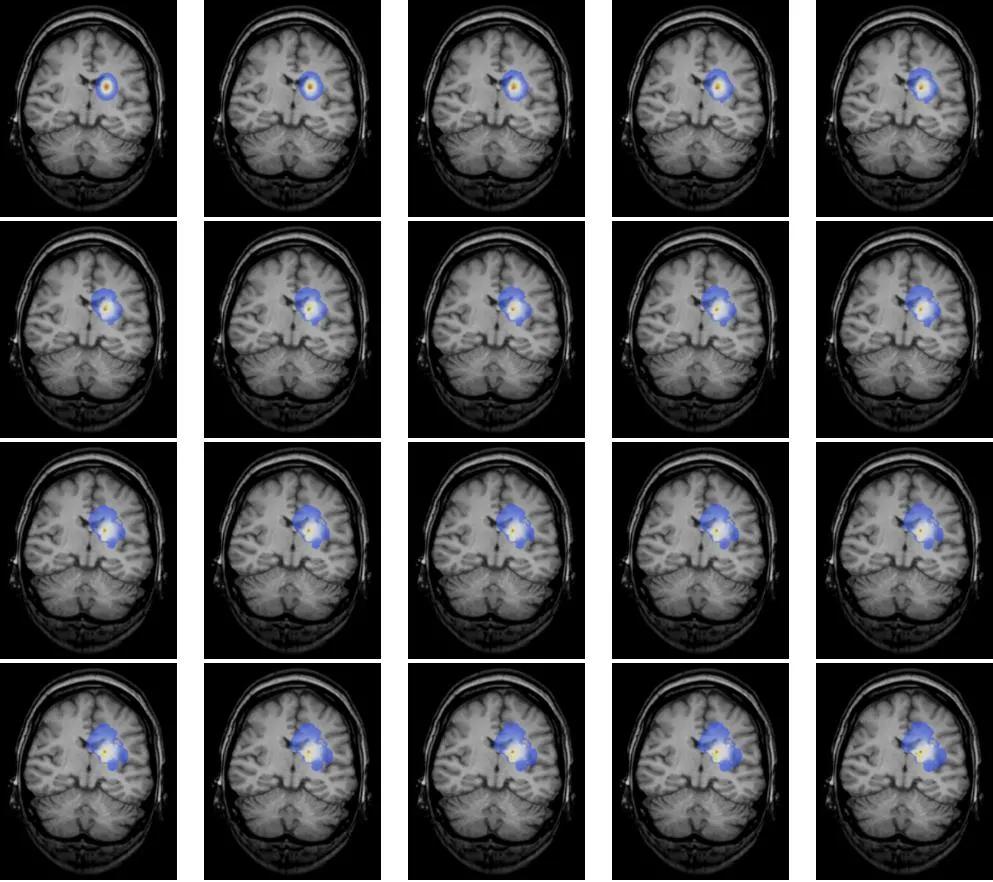

国外的脑科学曾利用扩散生长模型模拟脑肿瘤生长,并得出如下图像,它演示了一个本来边界清晰、影响范围不算特别大的脑瘤经过一段时间的发展可能会演变成边界不清、波及范围更广的全过程,这也说明了肿瘤不仅会生长,还极有可能升级恶化!

脑瘤不及时手术能长多大?一图看清

脑肿瘤发展进程如何?不及时手术切除能长多大?很多人对此并没有什么概念,你可以想象,中国成年人正常头围才54-58cm,而居然有人的脑瘤从左脑一直长到了右脑,最长直径达11cm,足足可以称霸脑瘤界!

白色高亮信号团块为肿瘤